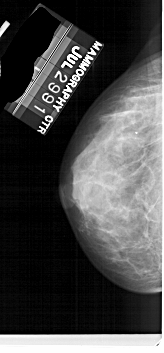

A_1734_1.RIGHT_MLO

RIGHT_MLO LINES 5221 PIXELS_PER_LINE 2461 BITS_PER_PIXEL 12 RESOLUTION 43.5 OVERLAY